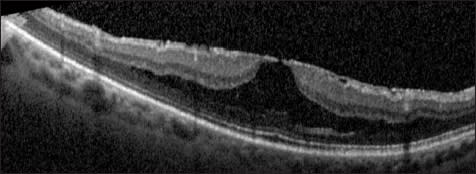

The progression of posterior vitreous detachment in otherwise normal eyes has been described and documented with OCT.3,4 First, the perifoveal hyaloid detaches from the macula, while remaining attached at the fovea (Figure 1). Next, the hyaloid detaches from the fovea but remains attached at the optic nerve head; the hyaloid is still visible on OCT at this stage as it remains close to the macula.

Figure 1. Normal eye. The posterior hyaloid is partially detached from the perifoveal region (arrow), with persistent attachment at the fovea and optic nerve. This is a normal stage of posterior vitreous detachment.